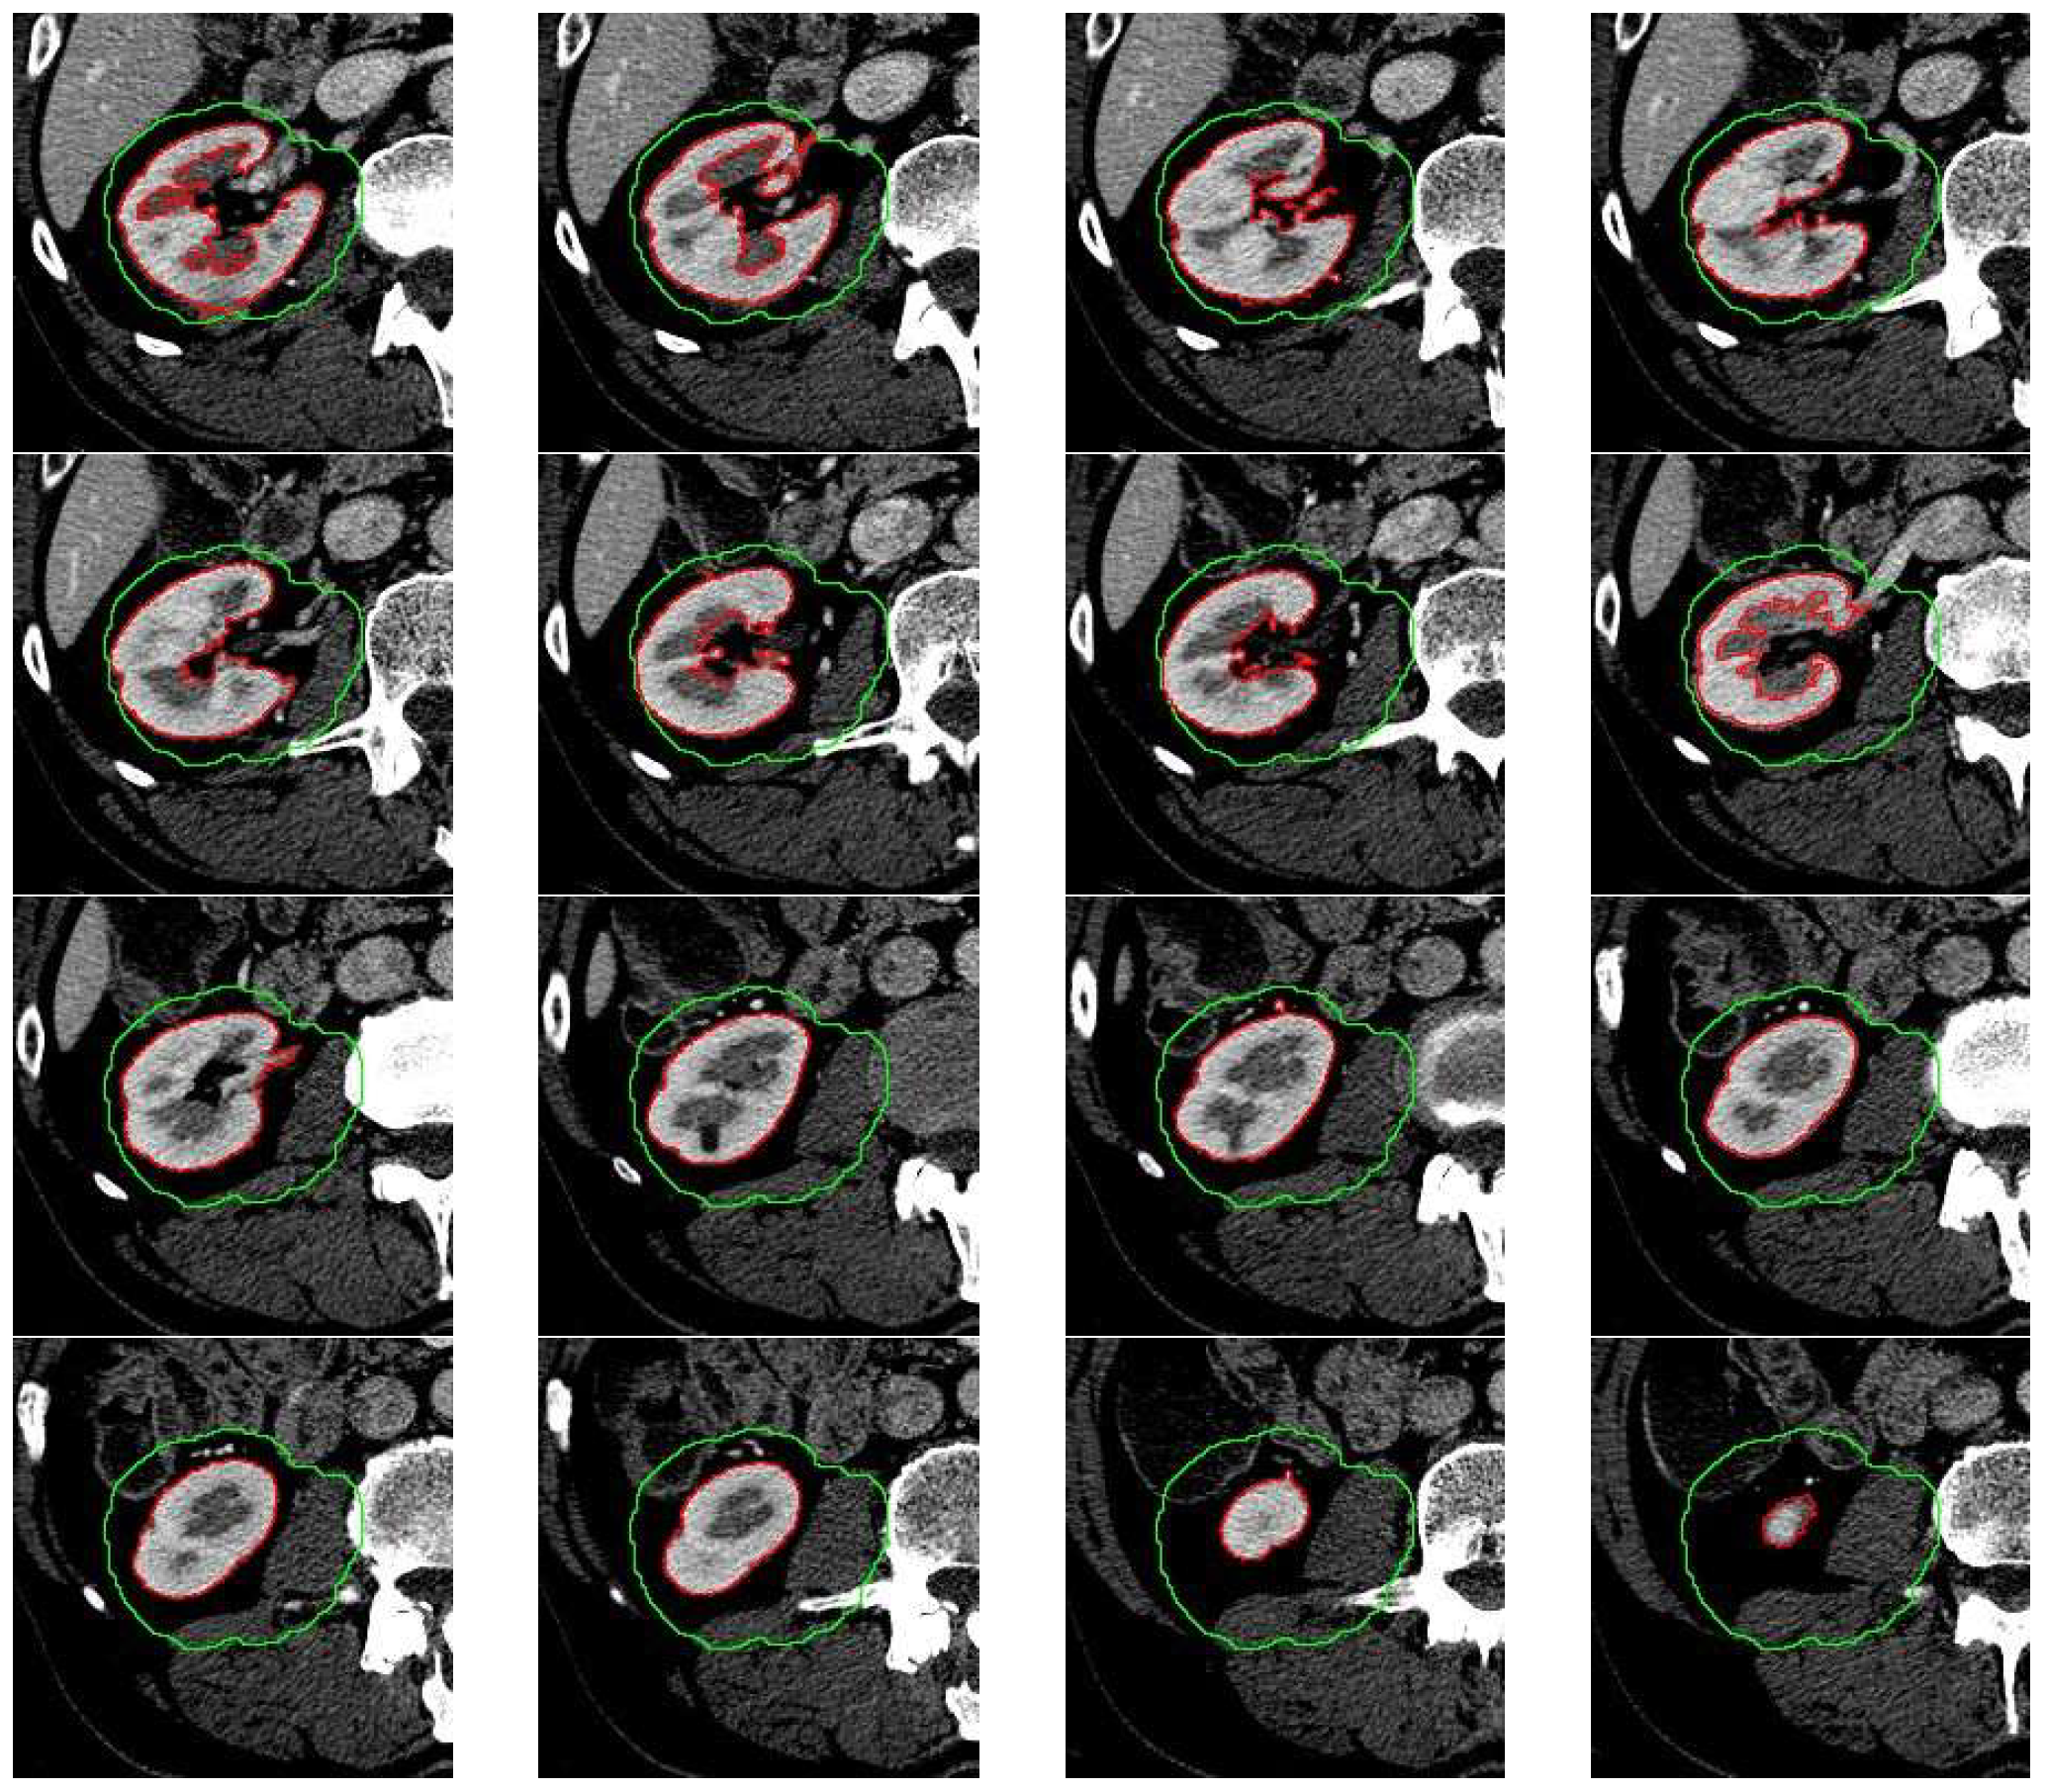

Figure 2 shows the result of the extended-maxima transform operation for selected H parameters. For each value of H, a s u m P value has been calculated. In the given example, we used as S m a square with the upper left corner position (x, y) = (50,175) and a side length of 200 pixels.

The next step is to leave one result for which s u m P is the highest and fill the holes and denote as H 0 the value of H . In the next step, the extended-maxima transform is executed again but in the raw C t s image. Each time algorithm is executed, the circularity coefficient P P is calculated and the result of the operation is removed from the image. According to this procedure, we generate u number of masks which are potential candidates for the final kidney mask. Finally, the mask of the highest P P value is selected. The result of the next five steps is shown in Figure 3.

Figure 2. The result of the extended-maxima transform operation for the selected parameters H = [30, 70, 110, 120, 140, 170]. The green frame shows an exemplary starting area S m .

Figure 3. The result of the next five steps of extended-maxima transforms and result in removing. For example, (a) is an original image, and examples (bf) show different shapes found in the next steps. The result of the operation is removed from the image after each step. The circularity factor P P is calculated for each result.